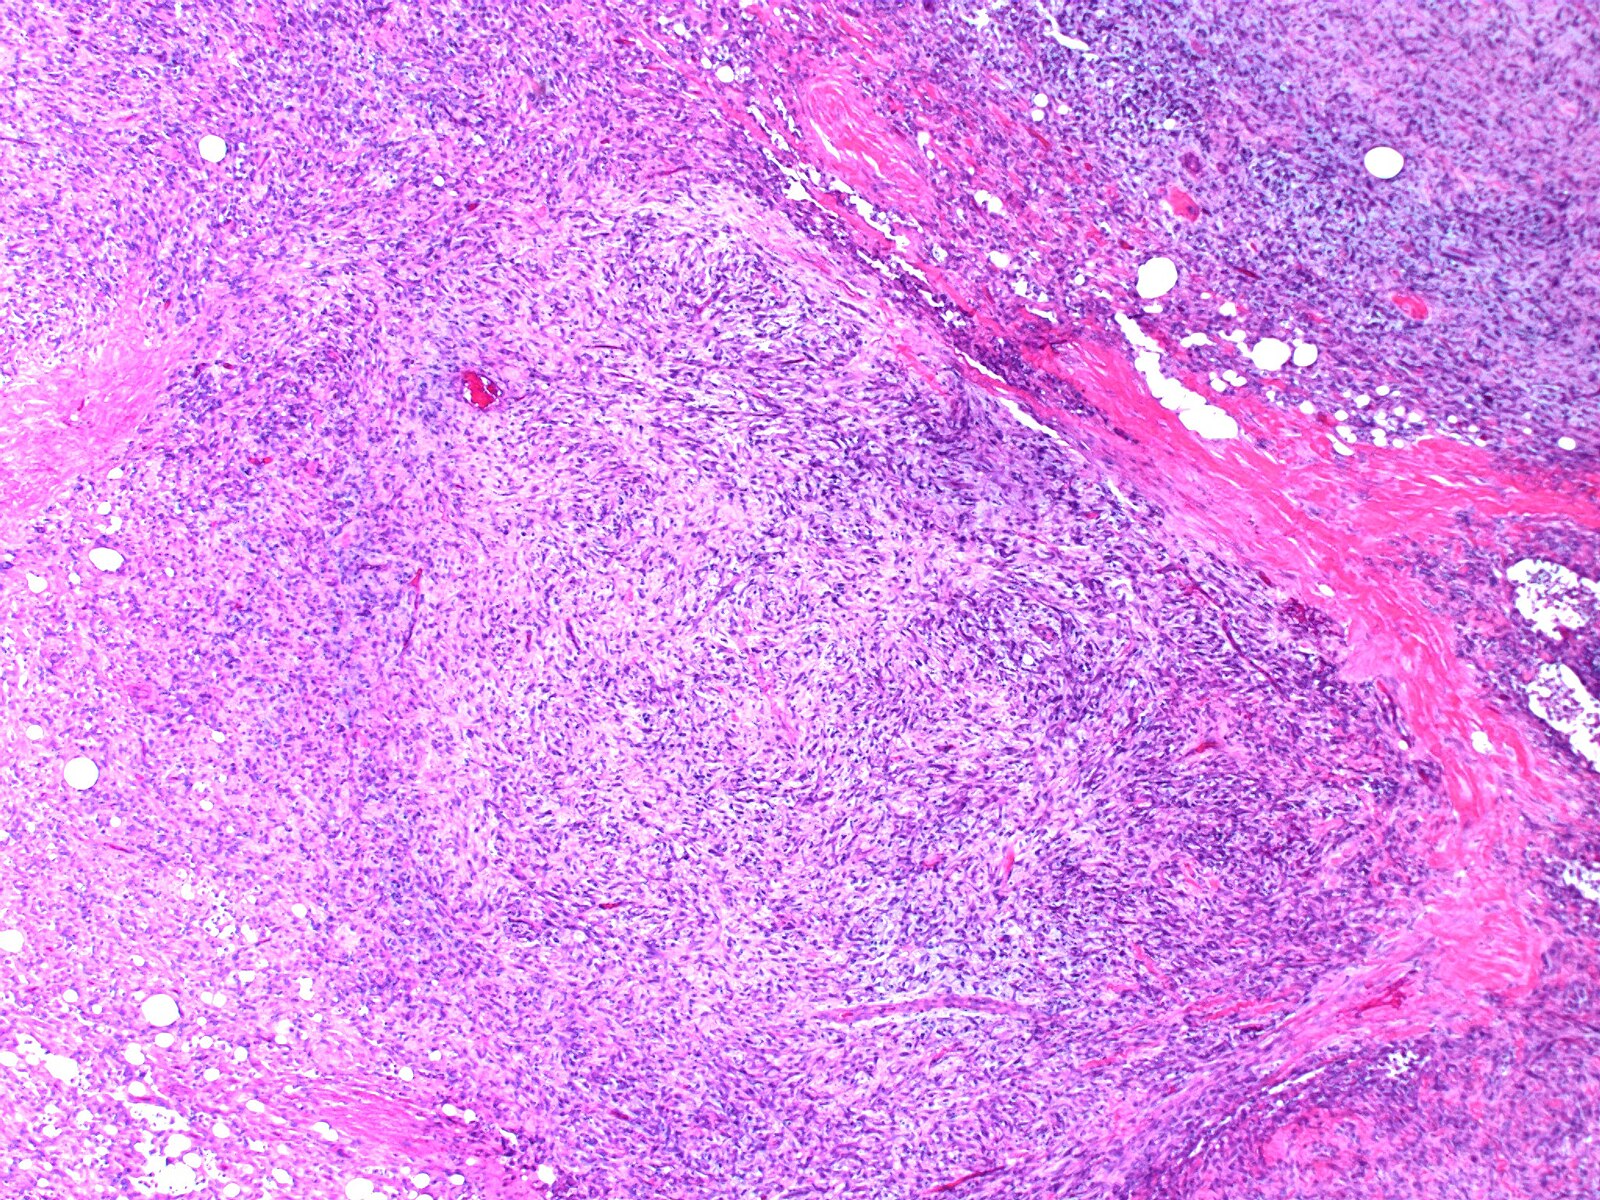

Sarcoidosis is a complex inflammatory disease that can affect multiple organs in the body. It is characterized by the formation of tiny clusters of inflammatory cells called granulomas. These granulomas can develop in any part of the body, but they most commonly affect the lungs and lymph nodes.

Why is a biopsy important in diagnosing sarcoidosis? A biopsy is crucial because it allows doctors to examine the affected tissue under a microscope and confirm the presence of granulomas, which are characteristic of sarcoidosis. This helps distinguish sarcoidosis from other conditions that may present with similar symptoms.